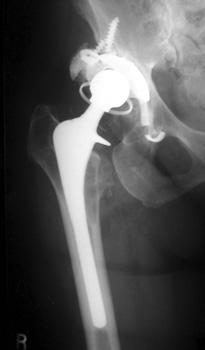

Side plate placed for periprosthetic fracture, now broken with loss of reduction of femur fracture

6/97

11/02